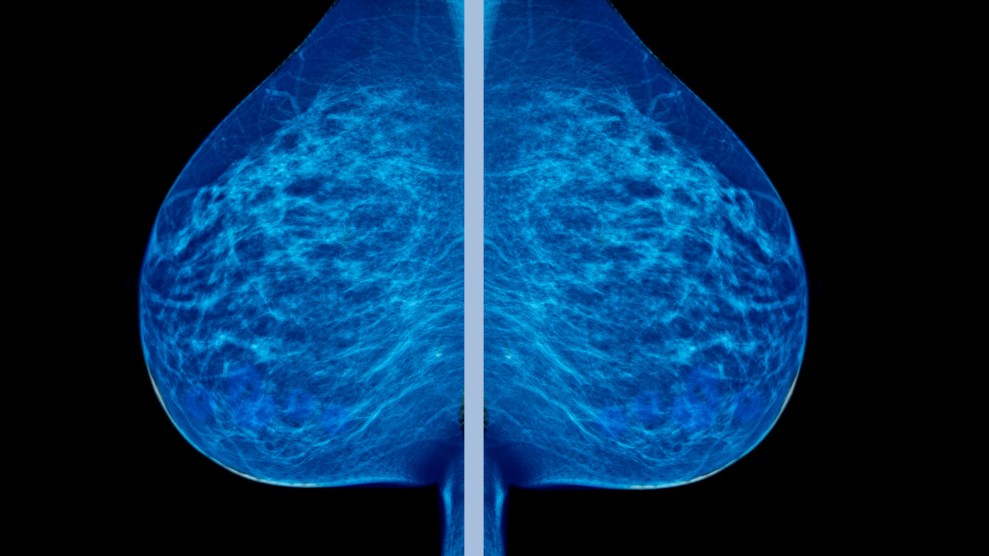

In a major shift following years of mounting evidence that women may be receiving too many mammograms, the American Cancer Society on Tuesday released new guidelines recommending that women start getting the tests later, at age 45, and only every other year.

The previous guidelines, which have been in place for decades, recommended that women begin the screenings at 40 and return annually. The organization also said women should opt out of routine breast examinations, where doctors check for abnormal lumps.

The significant changes are based on studies showing that overtesting can lead to false positives, sometimes leading women to undergo unnecessary tests, such as biopsies.